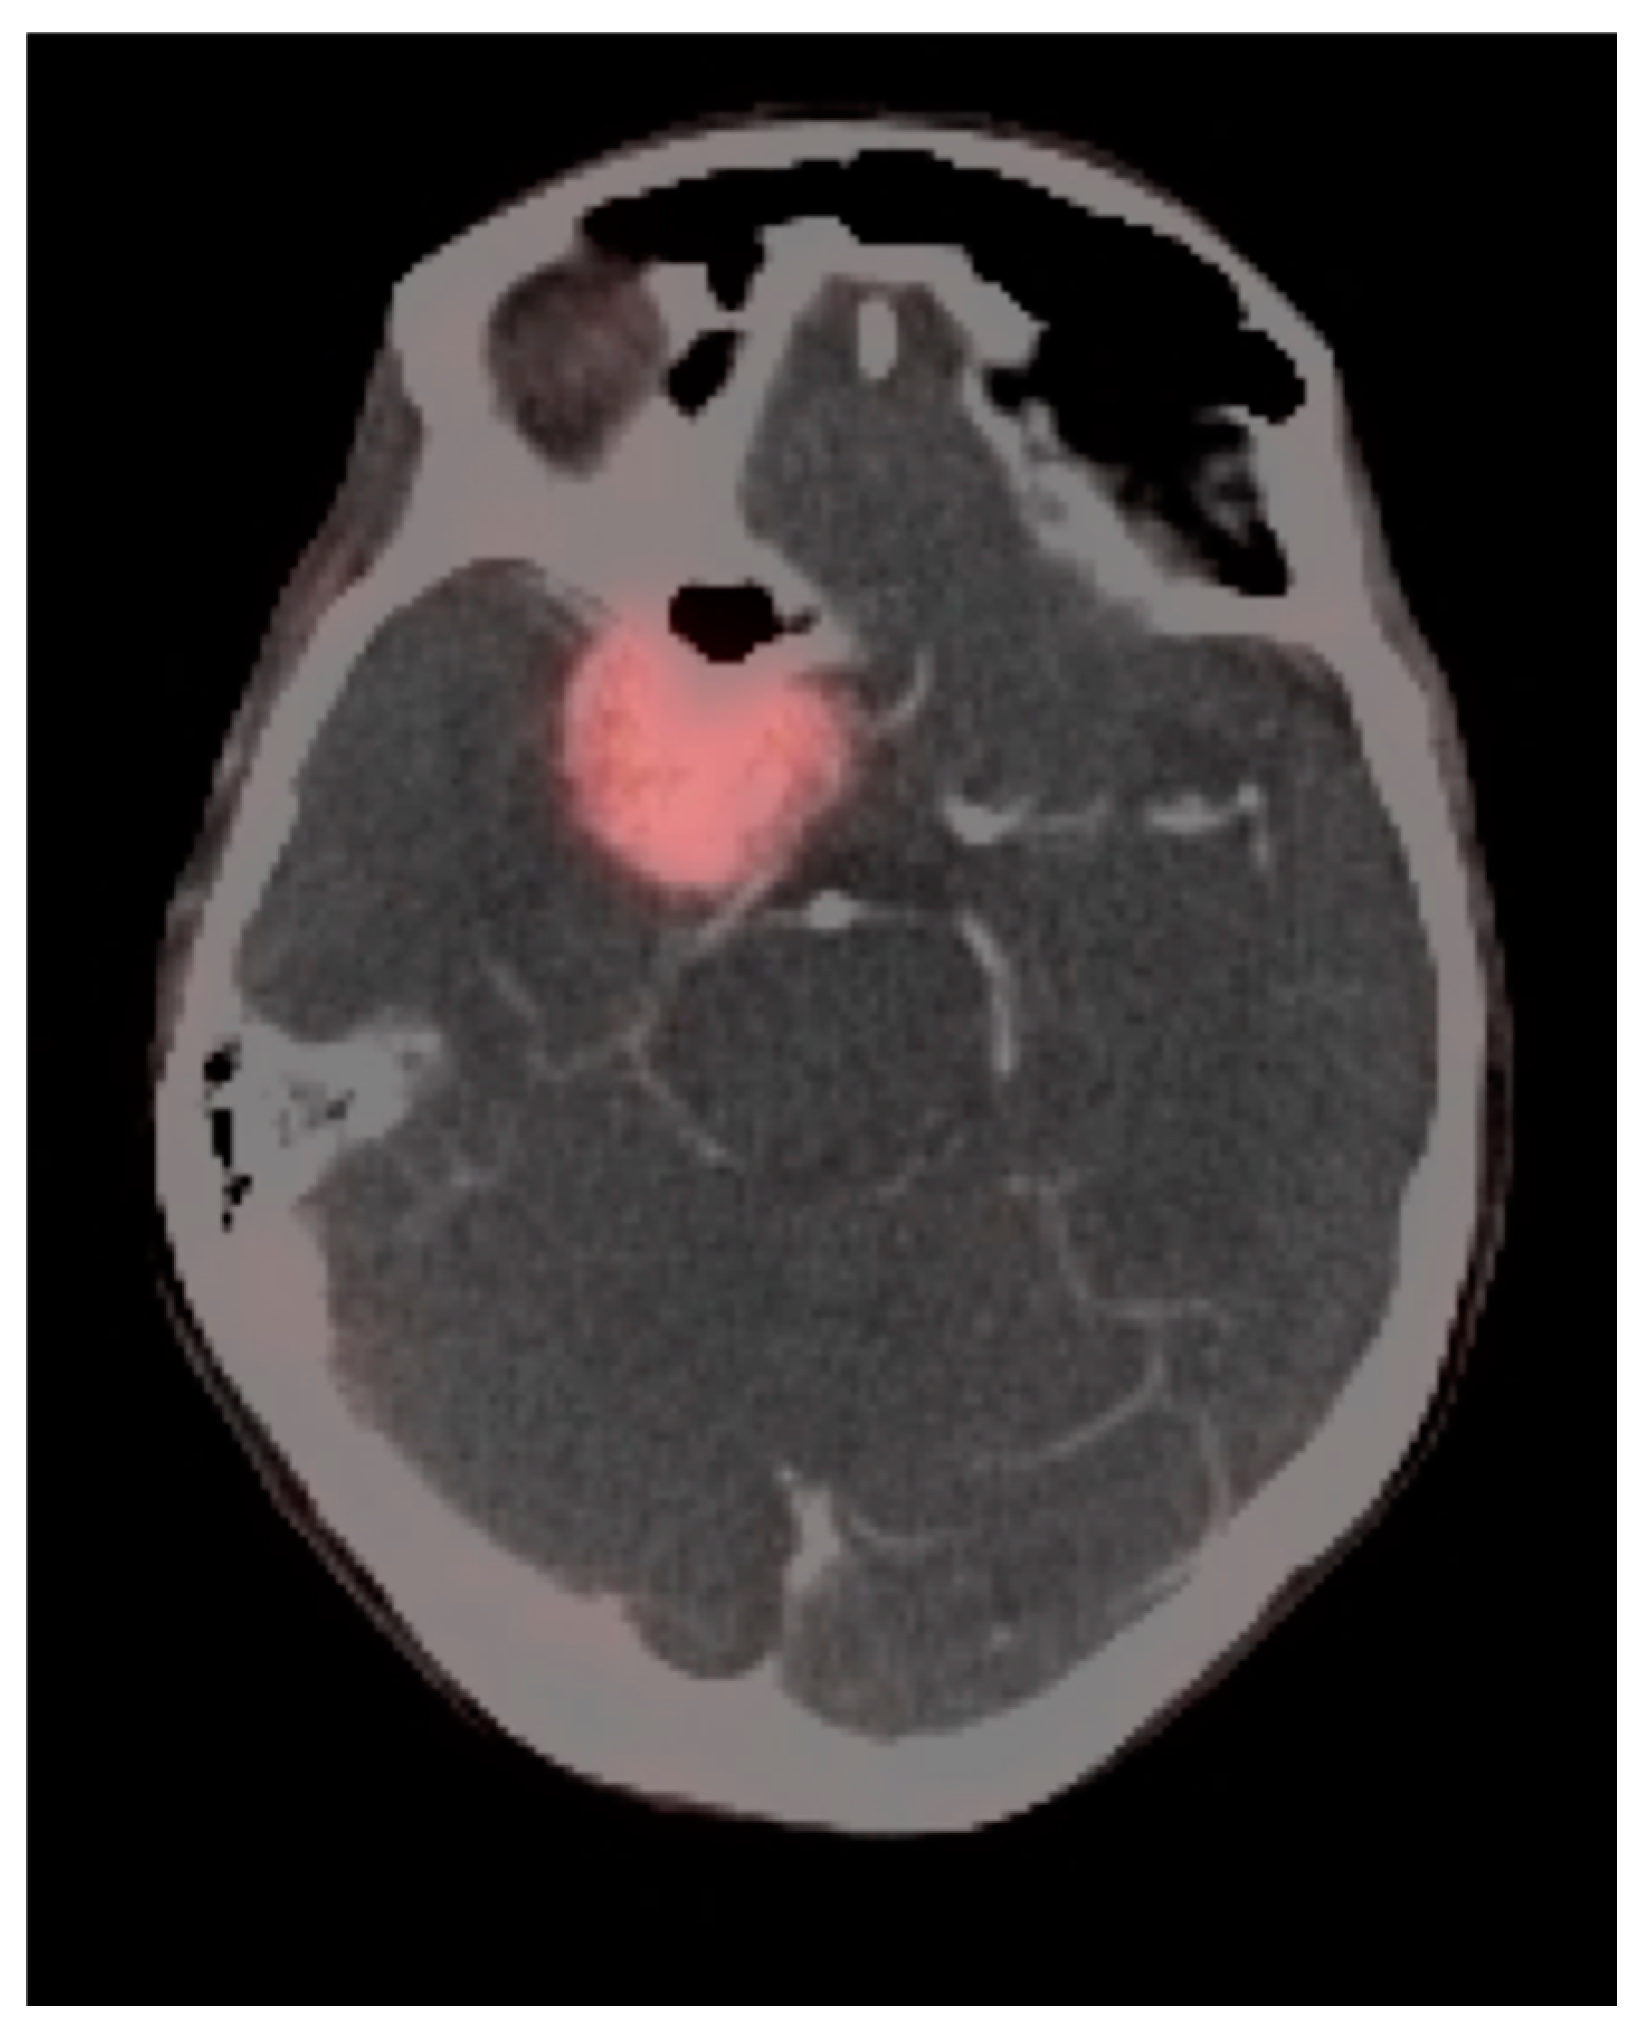

3.2. Paraneoplastic CNS Manifestations and Sources of False Positive FDG PET Scans That Can Mimic Brain Tumors

3.3. Primary Brain Tumors

3.4. CNS Lymphoma

3.7. Meningioma